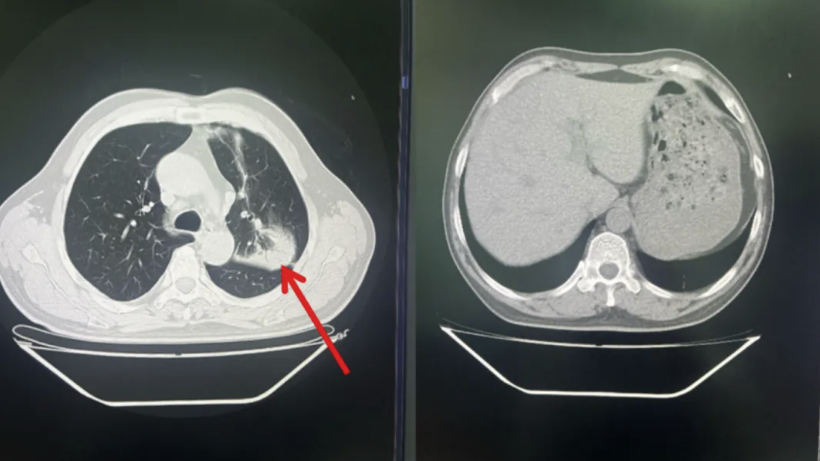

患者入院时以寒战、高热为主要表现,结合实验室检查及影像学检查,临床诊断考虑为社区获得性肺炎。入院后选用哌拉西林/他唑巴坦经验性抗感染治疗,3天后患者症状无明显好转,仍持续发热,体温最高达40.2℃,复查胸部CT示左肺上叶病灶范围明显扩大,左侧胸腔可见少量积液(见图2)。

图2:左肺上叶病灶范围明显扩大,左侧胸腔可见少量积液